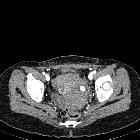

Radiographic features